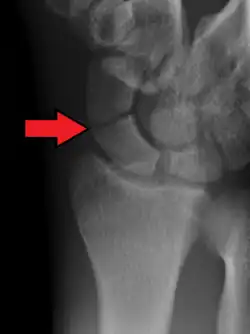

Fracture of the tubercle of the scaphoid bone of the wrist

Scaphoid fractures are often diagnosed using plain radiographs and multiple views are obtained as standard.[9] However, not all fractures are apparent initially.[7] In 1/4 of cases, the clinical examination suggests a fracture, but the X-ray does not show it, even though there is indeed a fracture.[10] Therefore, people with tenderness over the scaphoid (those who exhibit pain to pressure in the anatomic snuff box) are often splinted in a thumb spica for 7–10 days at which point a second set of X-rays is taken.[7] If a minimally displaced fracture was present initially, healing will now be apparent. Even then a fracture may not be apparent. A CT Scan can then be used to evaluate the scaphoid with greater resolution. The use of MRI, if available, is preferred over CT and can give one an immediate diagnosis.[11] Bone scintigraphy is also an effective method for diagnosis fracture which do not appear on Xray.[12]